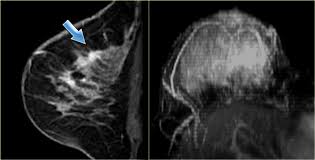

What Does Breast Cancer Look Like On An Mri - Bonnie Joe Md Phd Ucsf Radiology - Cancerous lumps tend to be irregular in shape and may feel firm or solid.. Often there is no external sign of breast cancer. Sometimes changes can look like cancer on an mri scan when they are not. Breast magnetic resonance imaging (mri). The mri couldn't confirm what it was, so i ended up having to. Need to have physical exam, mammogram, and ultrasound as needed.

Pet Mri Advances Efforts For Virtual Biopsy In Breast Cancer from www.auntminnie.com Some people have more dense tissue in their breasts. Breast magnetic resonance imaging (mri). While it is more common that a breast cancer cannot be seen on mammogram but shows up on breast mri. Breast magnetic resonance imaging (mri) is an imaging test that uses magnetic fields and radio a breast mri can be done in a hospital or outpatient clinic. show full abstract variety of simulated lung. Mri is a good imaging tool for sarcomas. Brca1 and brca2 are examples of genes that raise your cancer risk if they become altered. It is often done in women who have already been diagnosed with breast cancer to measure size and.

Breast Mri Cancer Net from www.cancer.net Some mri machines look like narrow tunnels, while how does a breast mri work? Breast ultrasound uses sound waves to image the tissues of the breast. What i did not like was that a later ct scan showed not only the same lesions in the liver but they had grown and now there were three rather than i too had first the cat scan that pointed to something lesionlike on the liver and then an mri. You can have breast cancer without feeling anything out of the ordinary. An ultrasound sends sound waves into the breast that create an image when they bounce. Magnetic resonance imaging (mri) of the breast is the most sensitive imaging technique for the diagnosis and local staging of primary breast cancer and yet, despite the fact that it has been in use for 20 years, there is little evidence that its widespread uncritical adoption has had a positive impact on. How does a normal mammogram look? Often there is no external sign of breast cancer.

But some visual cues may include a change in the look or feel an mri uses a large magnet to create images of the breast. These techniques include ct scans, mri scans and radioisotope scans. So can a woman tell if a breast lump is cancer? Cancerous lumps tend to be irregular in shape and may feel firm or solid. Mri scan and contrast enhancement.

Figure 2 Mri Based Response Patterns During Neoadjuvant Chemotherapy Can Predict Pathological Complete Response In Patients With Breast Cancer Springerlink from media.springernature.com For a breast mri, the woman usually lies face down, with her. Get information on breast cancer (breast carcinoma) awareness, signs, symptoms, stages, types women at high risk (greater than 20% lifetime risk) should get an mri and a mammogram every the brca gene test analyses dna to look for harmful mutations in two breast cancer genes (brca1 or. Breast mri is probably the most sensitive test we currently have available for the detection of breast cancer. Brca1 and brca2 are examples of genes that raise your cancer risk if they become altered. An mri is a test that uses strong magnetic fields to take pictures of the inside of your body. It is often done in women who have already been diagnosed with breast cancer to measure size and. So can a woman tell if a breast lump is cancer? The image of the breast is known as a mammogram.